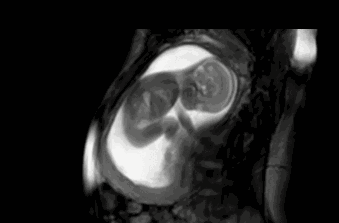

为什么会长妊娠纹?

妊娠纹主要是怀孕期间准妈妈的皮肤过度扩张,使得弹力纤维断裂 。像准妈妈皮肤弹性不够,或者孕期体重增长过快,都会导致这弹力纤维断裂的现象发生 。